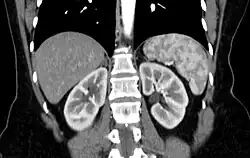

Der Begriff Tigermilz wird in der Röntgendiagnostik bei der Computertomographie verwendet und bezeichnet die fleckige, marmorierte Darstellung der Milz in der arteriellen Kontrastmittelphase. Dabei handelt es sich nicht um einen krankhaften Befund. Vielmehr entsteht das Bild durch die unterschiedliche schnelle Anflutung des Kontrastmittels in der Pulpa- und Trabekelstruktur der Milz.